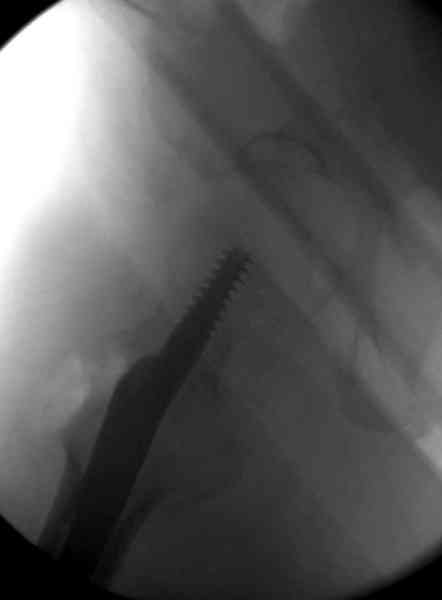

Здесь сканнированные снимки импланта и операционные снимки больной.